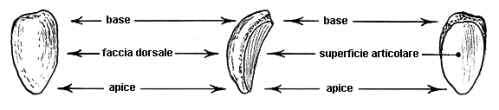

– la rotula: di forma ovale, è alloggiata nella troclea femorale. Piuttosto appiattita, presenta due facce, una dorsale (che è quella che guarda in avanti) ed una articolare (ovvero quella che, rivestita di cartilagine articolare, le permette di scorrere nella troclea femorale). E’ praticamente avvolta da tessuto fibroso, che nella parte superiore si continua con il tendine del quadricipite femorale (tendine rotuleo), mentre all’apice inferiore dà inizio al legamento patellare, che per intenderci è quello che ha ceduto nel famoso ginocchio di Ronaldo e che termina sulla già citata cresta tibiale.